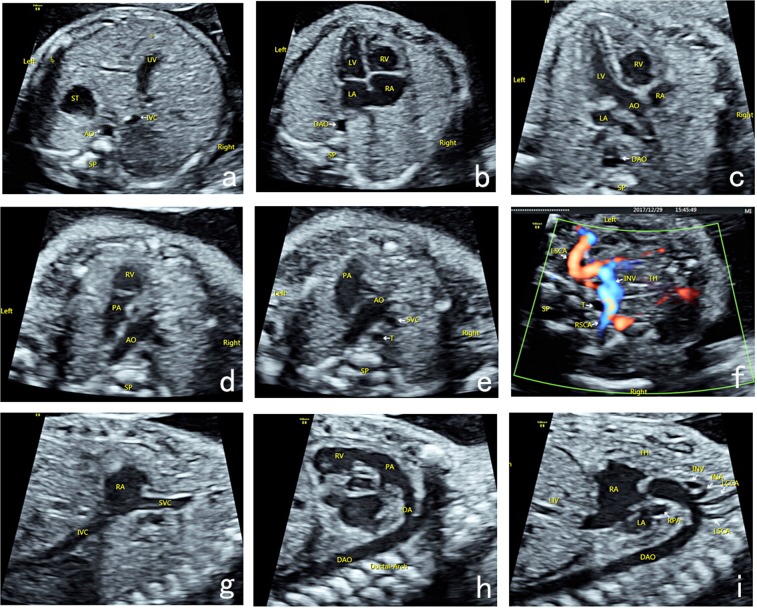

Ultrasound examination was performed by physicians with prenatal ultrasound diagnostic qualifications using GE Voluson E8 (GE Healthcare, Lafayette, CO, USA), Philips iU22 (Philips, Copenhagen, Denmark), Siemens Acuson Sequoia 512 (SIEMENS, Munich. Germany), or S2000 (SIEMENS, Munich, Germany) Color Doppler Ultrasound with 2D/3D volume probe (frequency: 4.0–8.0 MHz). The prenatal ultrasound analysis of nine-segment-sequential method included nine basic sections (Fig. 1a–i): transverse section of upper abdomen, four-chamber heart section, left ventricular outflow tract section, right ventricular outflow tract section, three-vascular-tracheal section, bilateral subclavian artery section, long axis section of superior and inferior vena cava, long axis section of aortic arch, and long axis section of ductus arteriosus.

Figure 1.

Nine-segment-sequential method for analysis of fetal heart ultrasound. Nine-segment-sequential method for analysis of fetal heart ultrasound included nine basic sections: transverse section of upper abdomen (a), four-chamber heart section (b), left ventricular outflow tract section (c), right ventricular outflow tract section (d), three-vascular-tracheal section (e), bilateral subclavian artery section (f), long axis section of superior and inferior vena cava (g), long axis section of ductus arteriosus (h), and long axis section of aortic arch (i). UV, umbilical vein; ST, stomach; IVC, inferior vena cava; AO, aortic; SP, spinal; DAO, descending aorta; LA, left atrium; RA, right atrium; LV, left ventricle; RV, right ventricle; PA, pulmonary artery; SVC, superior vena cava; T, trachea; TH, thymus; LSCA, left subclavian artery; RSCA, right subclavian artery; IVC, inferior vena cava; DA, ductus arteriosus; INV, innominate vein; INA, innominate artery; LCCA, left common carotid artery; LSCA, left subclavian artery.